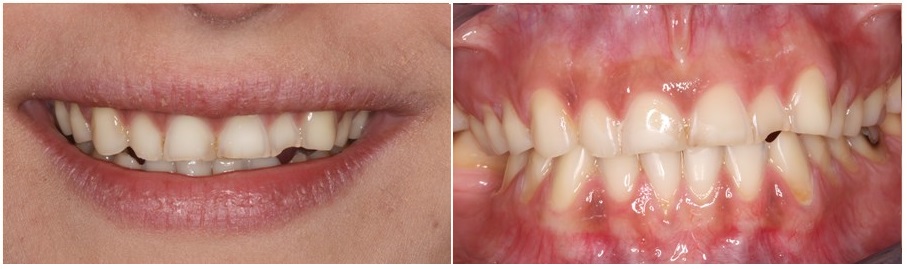

The following picture presents teeth with significant erosion due to excessive vomiting during the two pregnancies of our patient. Teeth have lost their shape and they have turned yellow in the areas where the enamel was lost.

The patient was unhappy with her smile, and she also had difficulty chewing as the teeth were reacting to all thermal stimuli, hot or cold.

The main reason that made her seek dental care, was smile esthetics. Her teeth appeared small and had rough incisal edges, that were fracturing often, exacerbating the problem day after day.

Most teeth had lost their enamel and a significant portion of dentin. Teeth had also lost their anatomical features while the height of the lower third of her face had decreased.

Old fillings were protruding over her teeth, ans some of the teeth were decayed.

Erosion had affected most of the maxillary and mandibular teeth.